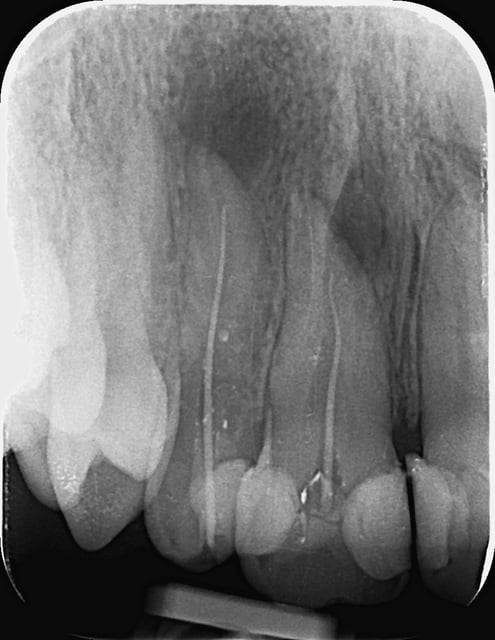

Bonjour a tout !

Initial e après obturation

lupusebastian écrivait:

> Bonjour a tout !

>

> Initial e après obturation

joli travail.

Obturation gutta à chaud j'imagine?

no !!! condensation latérale à froid est alors verticale chaud... e buildup